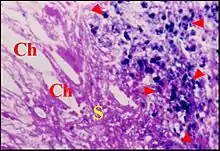

Lésion prédominante, elle est caractérisée au début par un simple œdème du stroma et une vaso-dilatation de ses capillaires. Un infiltrat inflammatoire non spécifique apparait ensuite dans le même stroma. Cet infiltrat se compose de polynucléaires neutrophiles, lymphocytes B, plasmocytes, mastocytes et histiocytes. Il peut former un ou plusieurs foyers granulomateux avec des capillaires néoformés, des fibroblastes et des hémorragies localisées.Des polynucléaires et cellules de Langherans en émigrent vers l’épithélium malpighien sus-jacent où leurs vimentine et proteine S100 permettent de bien les mettre en évidence. L’afflux de ces cellules inflammatoires peut entrainer des ruptures épithéliales spontanées (ulcérations) et confirme leur agressivité envers le revêtement malpighien[8].

Le stroma granulomateux ainsi mis à nu peut s’épaissir en un ou plusieurs bourgeons charnus dont la protrusion forme un « polype otique » ou « aural ». Localisée ou diffuse, modérée ou sévère, l’inflammation ne se limite pas aux zones évolutives du cholestéatome[8]). De plus, elle peut affecter la chaine ossiculaire sous-jacente et, dans certains cas, les prothèses qui y ont été insérées.